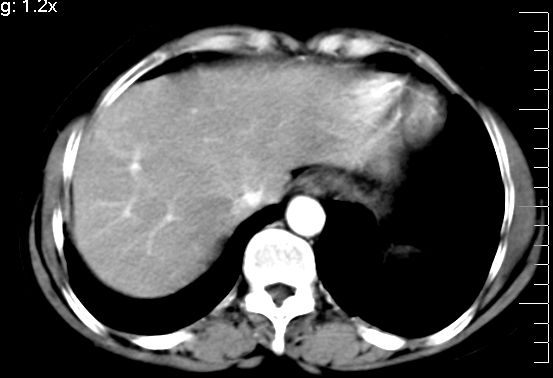

f、52岁,反复上腹部疼痛2年。肺结核病史10多年,胸片双上肺结核纤维化。

ct表现:

肝大小形态未见异常,肝内外胆管无扩张,肝s8段见一动脉期明显血管样强化结节,门脉期呈高密度,延迟期呈等密度,胆囊不大,增强扫描见胆囊及胆囊颈管壁增厚,有强化。

双肾灌注良好,代谢增快,动脉期肾盂见造影剂,左肾下极背侧见一略低密度病灶,延迟期见似不强化囊肿,双侧肾上腺未见异常。

胰腺及脾未见异常。肾门水平腹膜后见小淋巴结。腹腔未见积液征象。